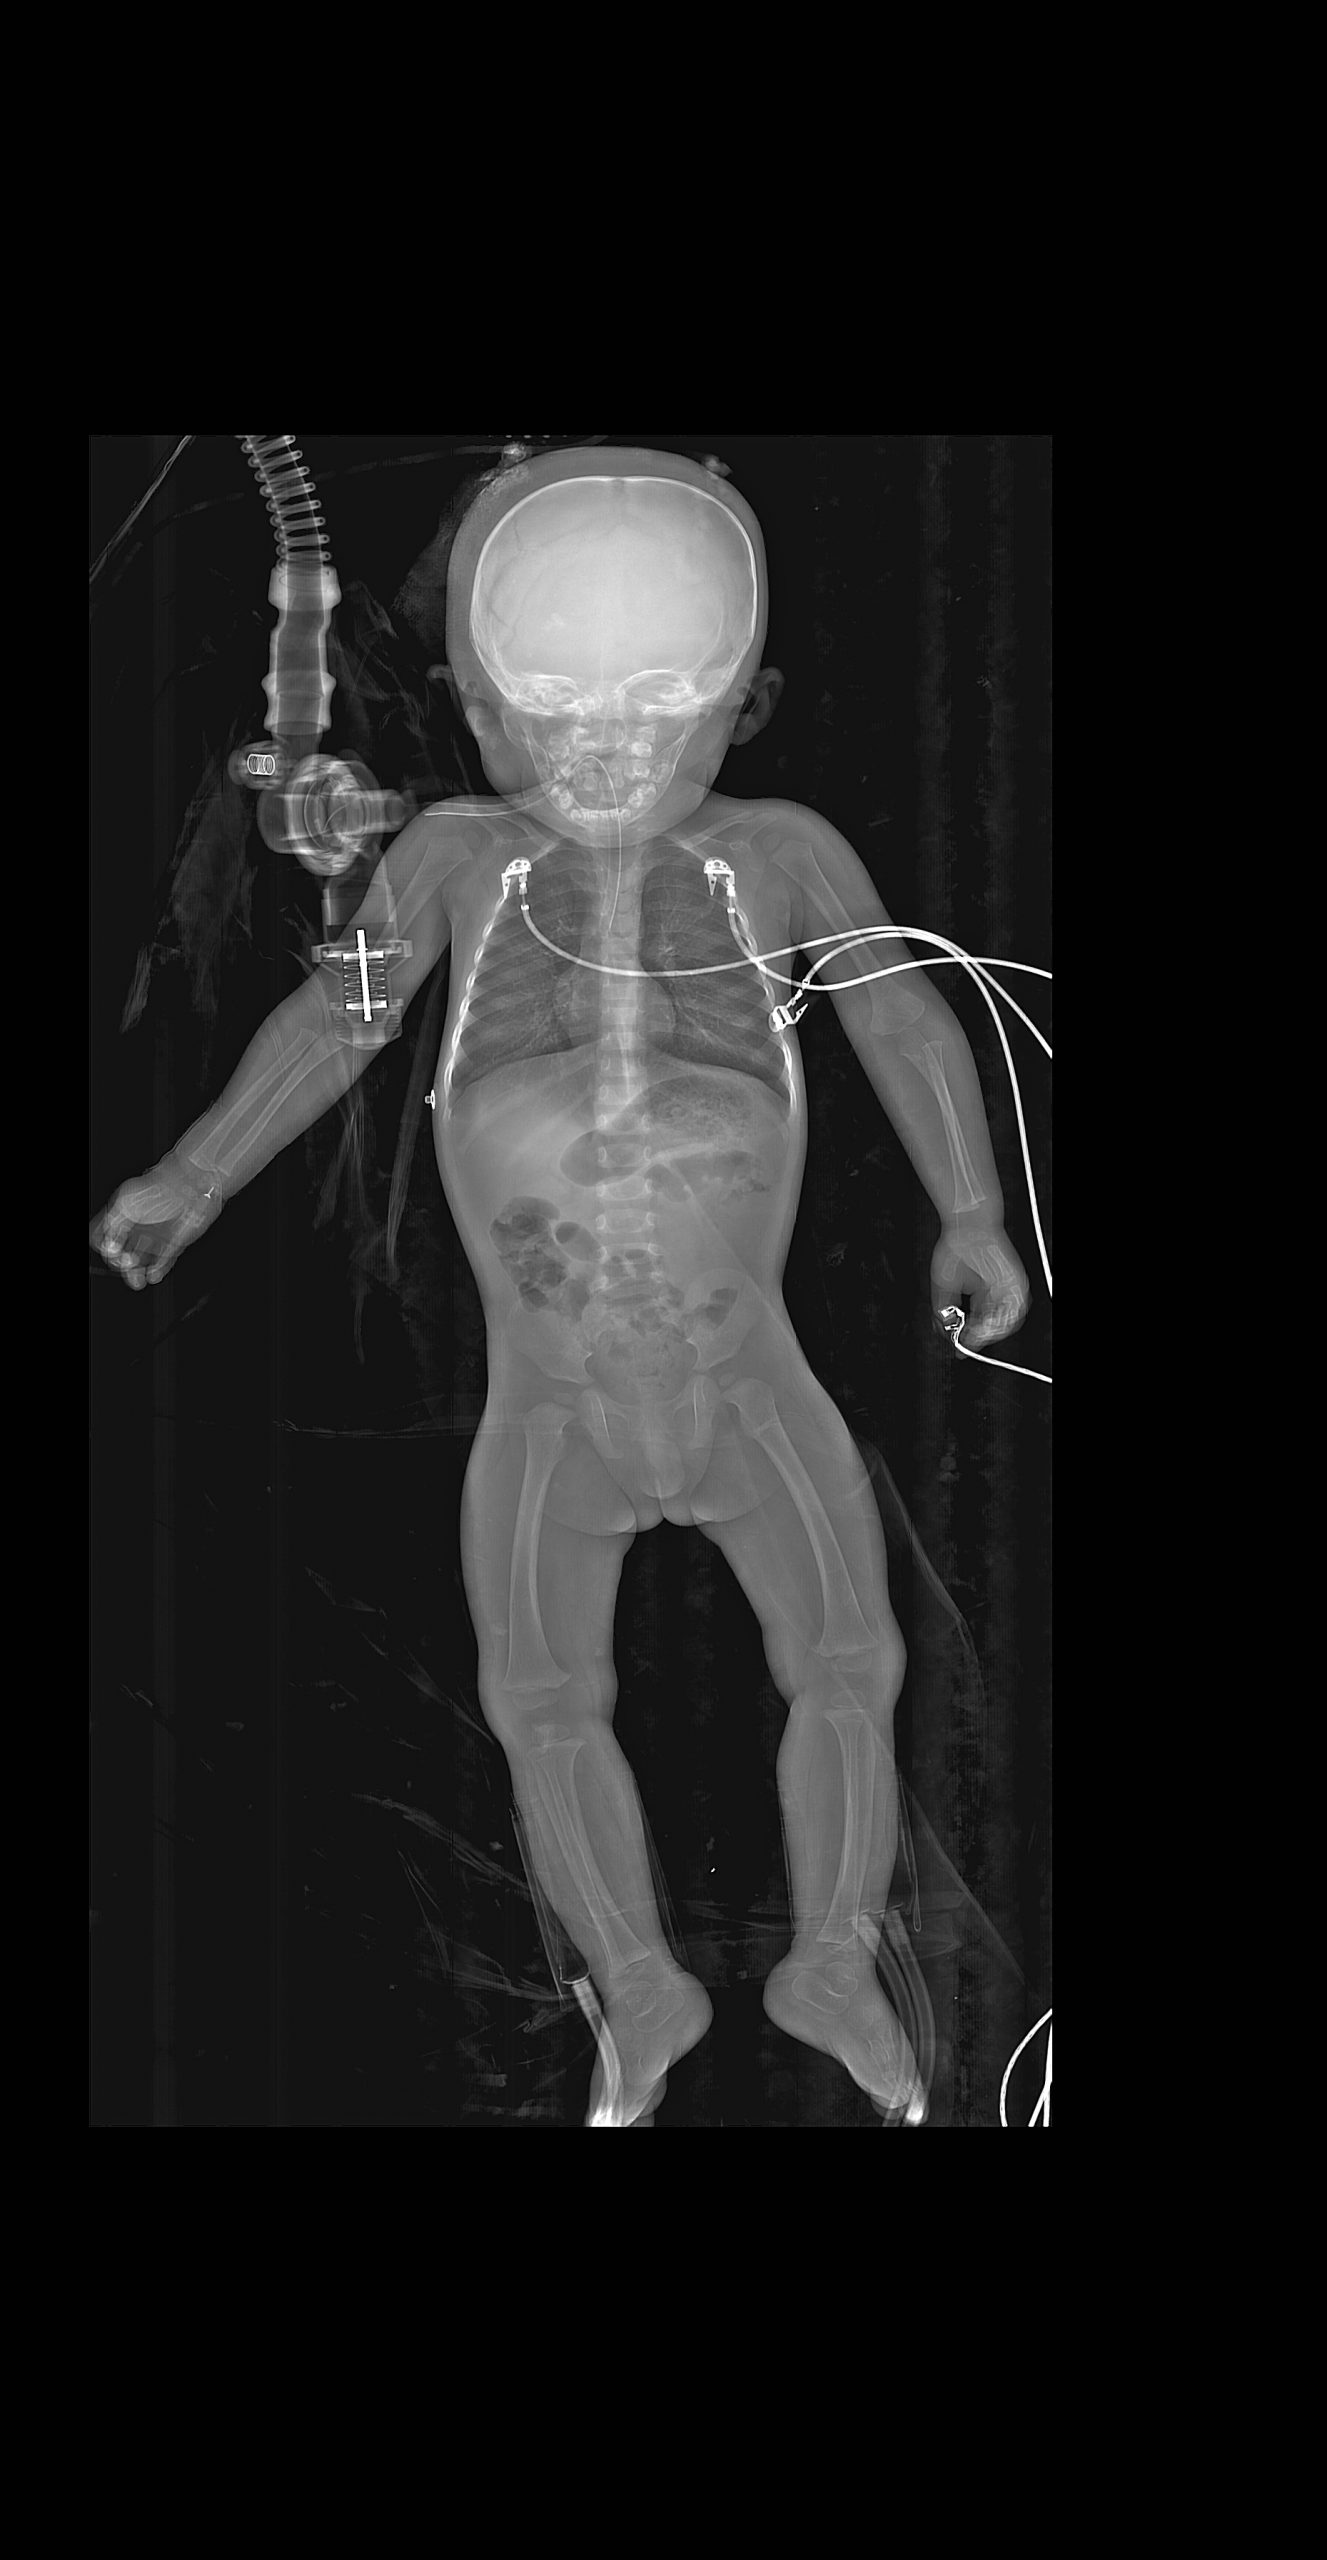

Klinik Görüntüler

Yukarıdaki örnek görüntüler, Lodox Xmplar-dr sisteminin her yaş ve vücut tipindeki hastalarda sunduğu yüksek çözünürlüklü tam vücut görüntüleme kapasitesini göstermektedir. Pediatrik hastalardan erişkinlere, düşük kilolu bireylerden yüksek vücut kitle indeksine sahip hastalara kadar geniş bir hasta grubunda net anatomik detay elde edilebilmektedir. Linear slot-scanning teknolojisi sayesinde kemik, yumuşak doku ve yabancı cisimler tek çekimde, ortalama 13–16 saniyede ve ultra düşük radyasyon dozu ile görüntülenir. Bu özellik, özellikle travma ve acil servis koşullarında hem hızlı tanı koymayı hem de radyasyona bağlı riskleri en aza indirmeyi mümkün kılar.